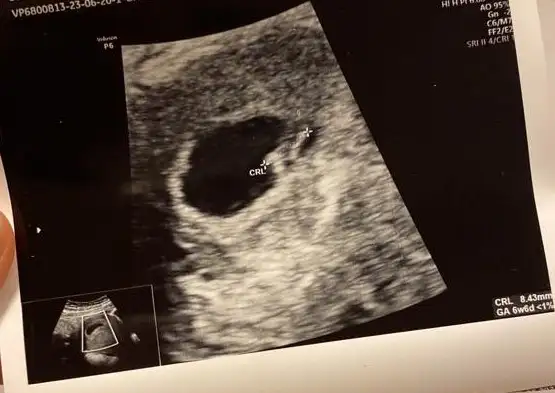

Merhaba, bizim kese görüntülerimiz hafta hafta bu şekilde şu an 7+1 deyiz, yorumlara bakınca kafam karıştı ne olabilir acaba? :)))

Eklentiler

• WhatsApp Image 2023-06-21 at 16.12.57.webp

WhatsApp Image 2023-06-21 at 16.12.57.webp

18,3 KB · Görüntüleme: 819